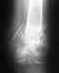

Выписалась с больницы с диагнозом: выраженные дегенеративно-дистрофические изменения в грудном отделе позвоночника в форме остеохондроза, спондилеза, спондилоартроза с клиновидной деформацией D7, D8, D9, D10, D11 позвонков,протрузиями дисков D7-8, D8-9, D9-10, грыжами Шморля.Верхнегрудной сколиоз 2 степени. В сравнении с предыдущими без динамики. При таком диагнозе положена ли мне инвалидность? Заранее спасибо.